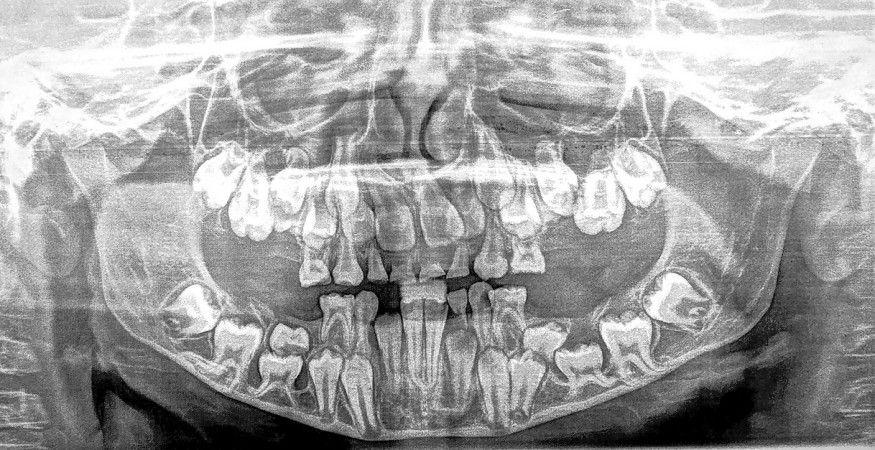

Les examens d’imagerie permettent de visualiser la présence de chemins d’éruption intra-osseux, coronairement aux dents permanentes concernées (fig. 2, 3). Une analyse fine des coupes obtenues par CBCT doit permettre d’exclure un phénomène d’ankylose ; la résolution spatiale doit donc être suffisante pour objectiver la présence d’un espace desmodontal préservé.

Fig. 2 – Radiographie panoramique initiale.Fig. 3 – Reconstruction 3D de l’arcade dentaire mandibulaire côté gauche.